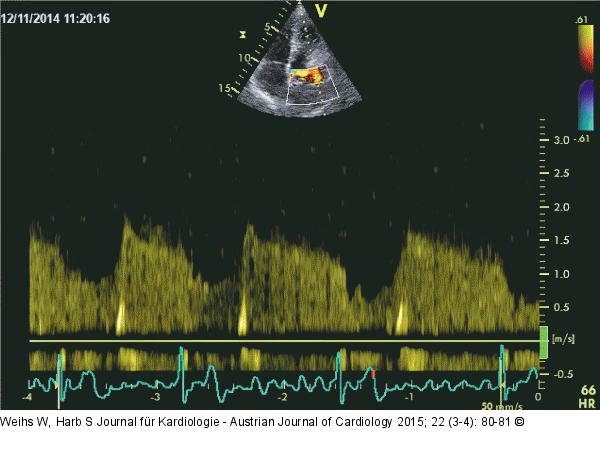

Abbildung 4: Membran

CW-Doppler: Erhöhte Geschwindigkeit über die Öffnung in der Membran im Sinne einer Stenose. |